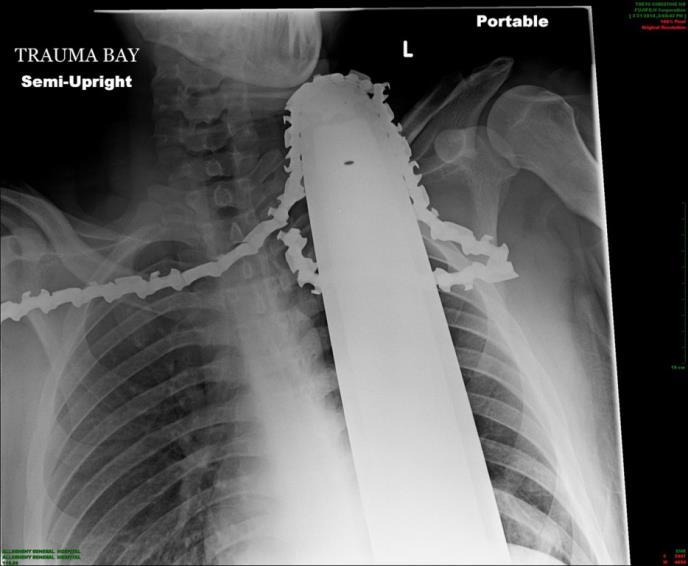

Doktori su saopštili da je lanac promašio velike krvne sudove, i povredio mu mišić. Bolnica je u utorak objavila rentgenski snimak na kojem se vidi lanac u vratu 21-godišnjeg drvošeče.